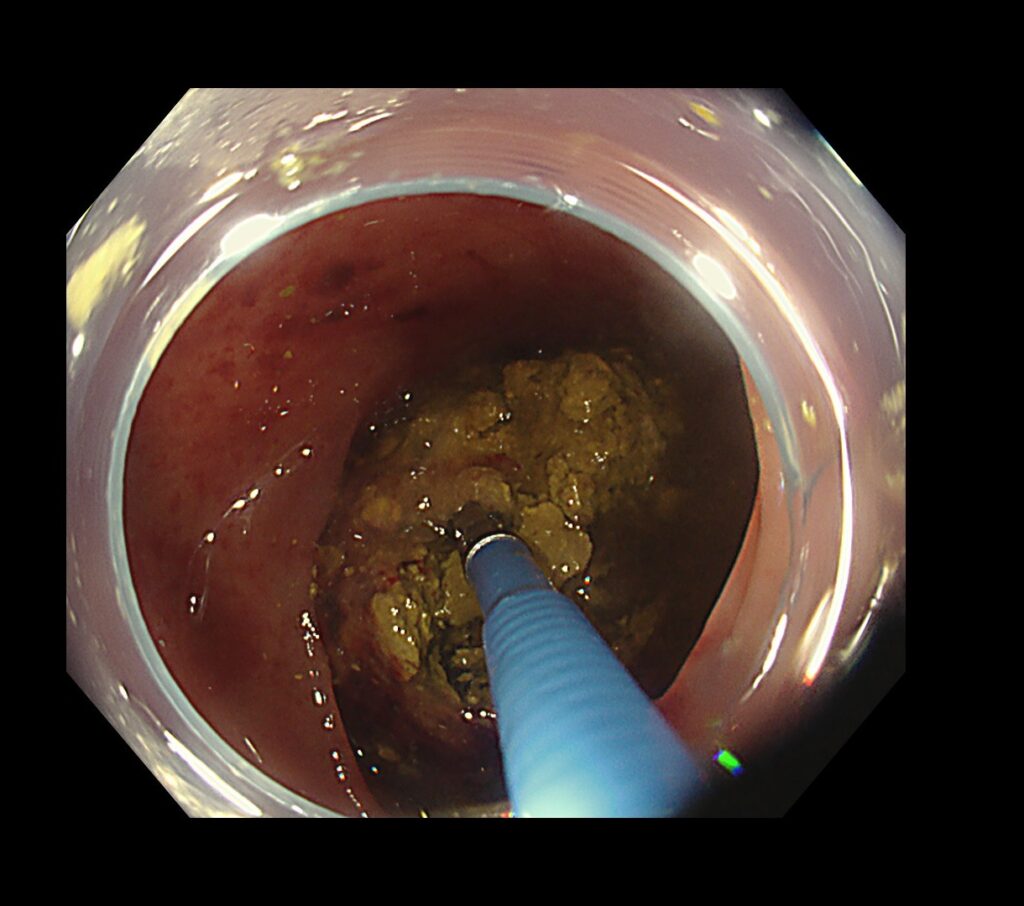

糞石による閉塞性大腸炎をきたしており、粘膜からの出血と腸に嵌頓する糞石を認めました。

糞石を内視鏡処置具で破砕していくと、何層にも重なり合う便の層を認めました。